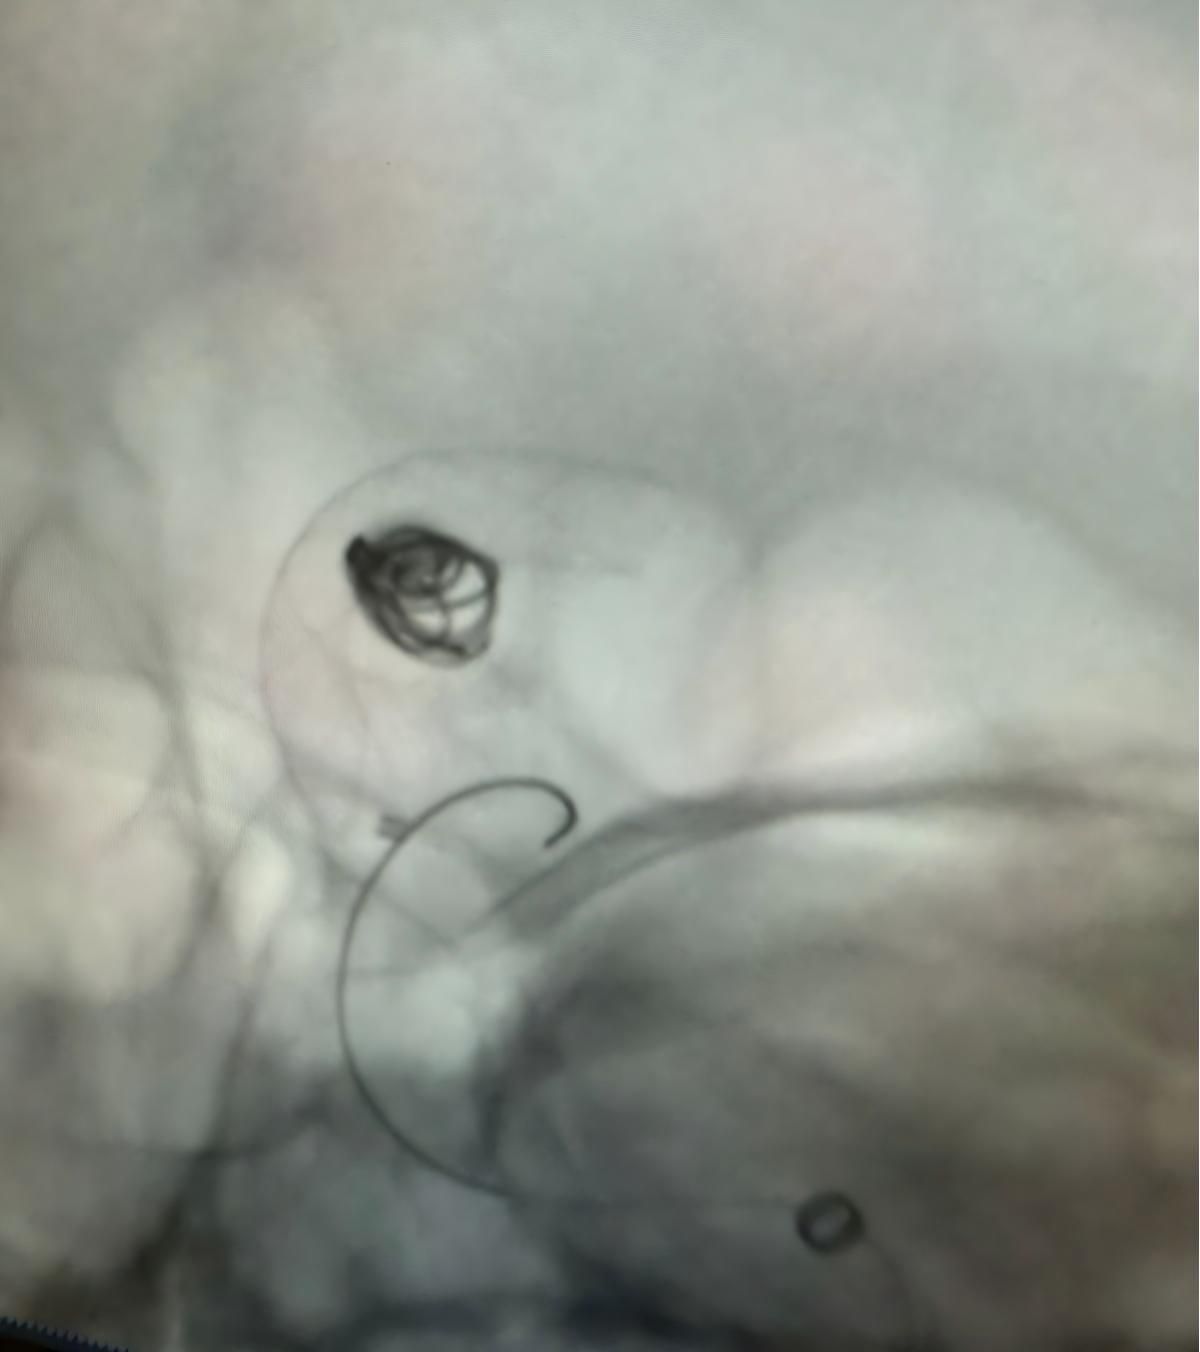

The treatment utilized the Nuva® Flow Diverter (TJED-D 5.0–14), Perdenser® 3D coil, and Frepass® Microcatheter (TJMC18 Plus) for a posterior communicating artery aneurysm.

Dr. Mutis highlighted the excellent visibility of the device and noted that retrieving was smooth. He expressed great satisfaction with the final outcome.